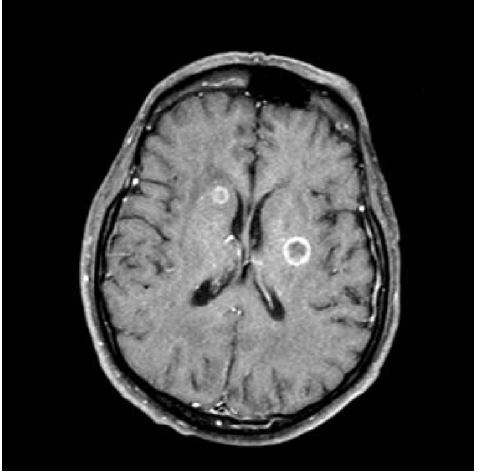

14

Q

-imaging modality -weight -orientation -window -body part -iv contrast -abnormality

A

-MRI -T1 -Axial - brain - brain -yes -metastatic small cell lung cancer

How well did you know this?